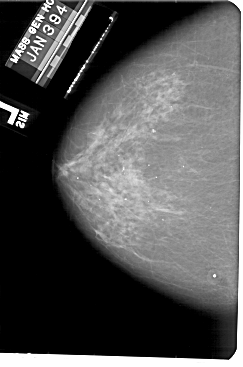

A_1901_1.RIGHT_CC

RIGHT_CC LINES 5491 PIXELS_PER_LINE 3511 BITS_PER_PIXEL 12 RESOLUTION 43.5 OVERLAY